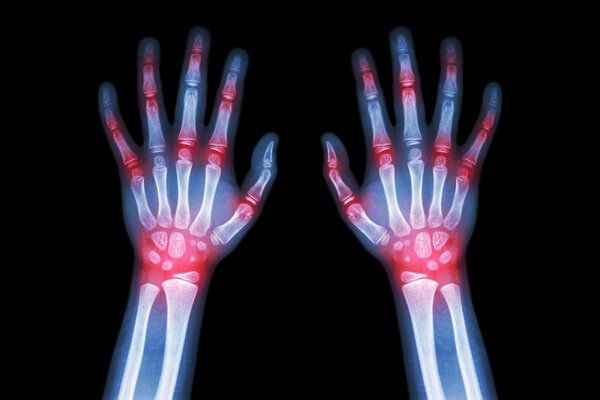

核心提示:类风湿病在缓解期和急性发作期的患者可以爬山,但不建议爬山。类风湿关节炎的临床表现主要是关节痛,关节痛的部位包括手指、手腕、膝盖、脚趾等,关节痛的特点是对称性、游走性。在类风湿关节炎缓解期,患者可以进行适当的功能锻炼,包括一些游泳、不负重的功能锻炼等。在类风湿关节炎的急性发作期,一般建议患者以休息为主

类风湿病在缓解期和急性发作期的患者可以爬山,但不建议爬山.类风湿关节炎的临床表现主要是关节痛,关节痛的部位包括手指、手腕、膝盖、脚趾等,关节痛的特点是对称性、游走性。在类风湿关节炎缓解期,患者可以进行适当的功能锻炼,包括一些游泳、不负重的功能锻炼等。在类风湿关节炎的急性发作期,一般建议患者以休息为主,避免过多的活动。如果爬山,可能会加重关节痛,不利于关节功能的恢复,因此不建议类风湿病患者爬山。